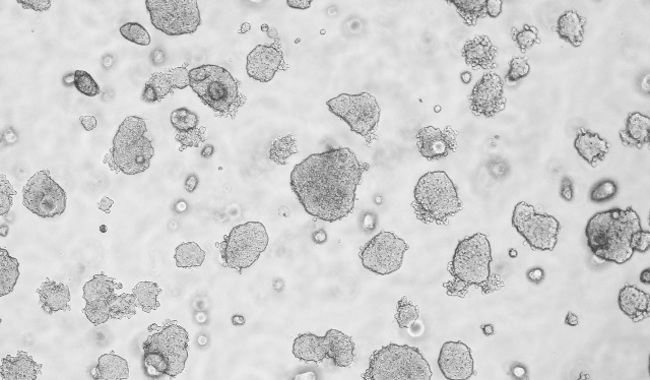

平板克隆形成圖像分析

平板克隆試驗是一種常用的測量細胞生長能力的技術,從開始已知的細胞群體監測菌落的形成。菌落的形成需要密集的分裂的原始細胞,所以在整個實驗的細胞或菌落的數量的量化是細胞的生長潛力的指標。因此,集落形成試驗已成為一種廣泛用于癌癥研究的方法來研究藥物和電離輻射療法對癌細胞增殖的影響。